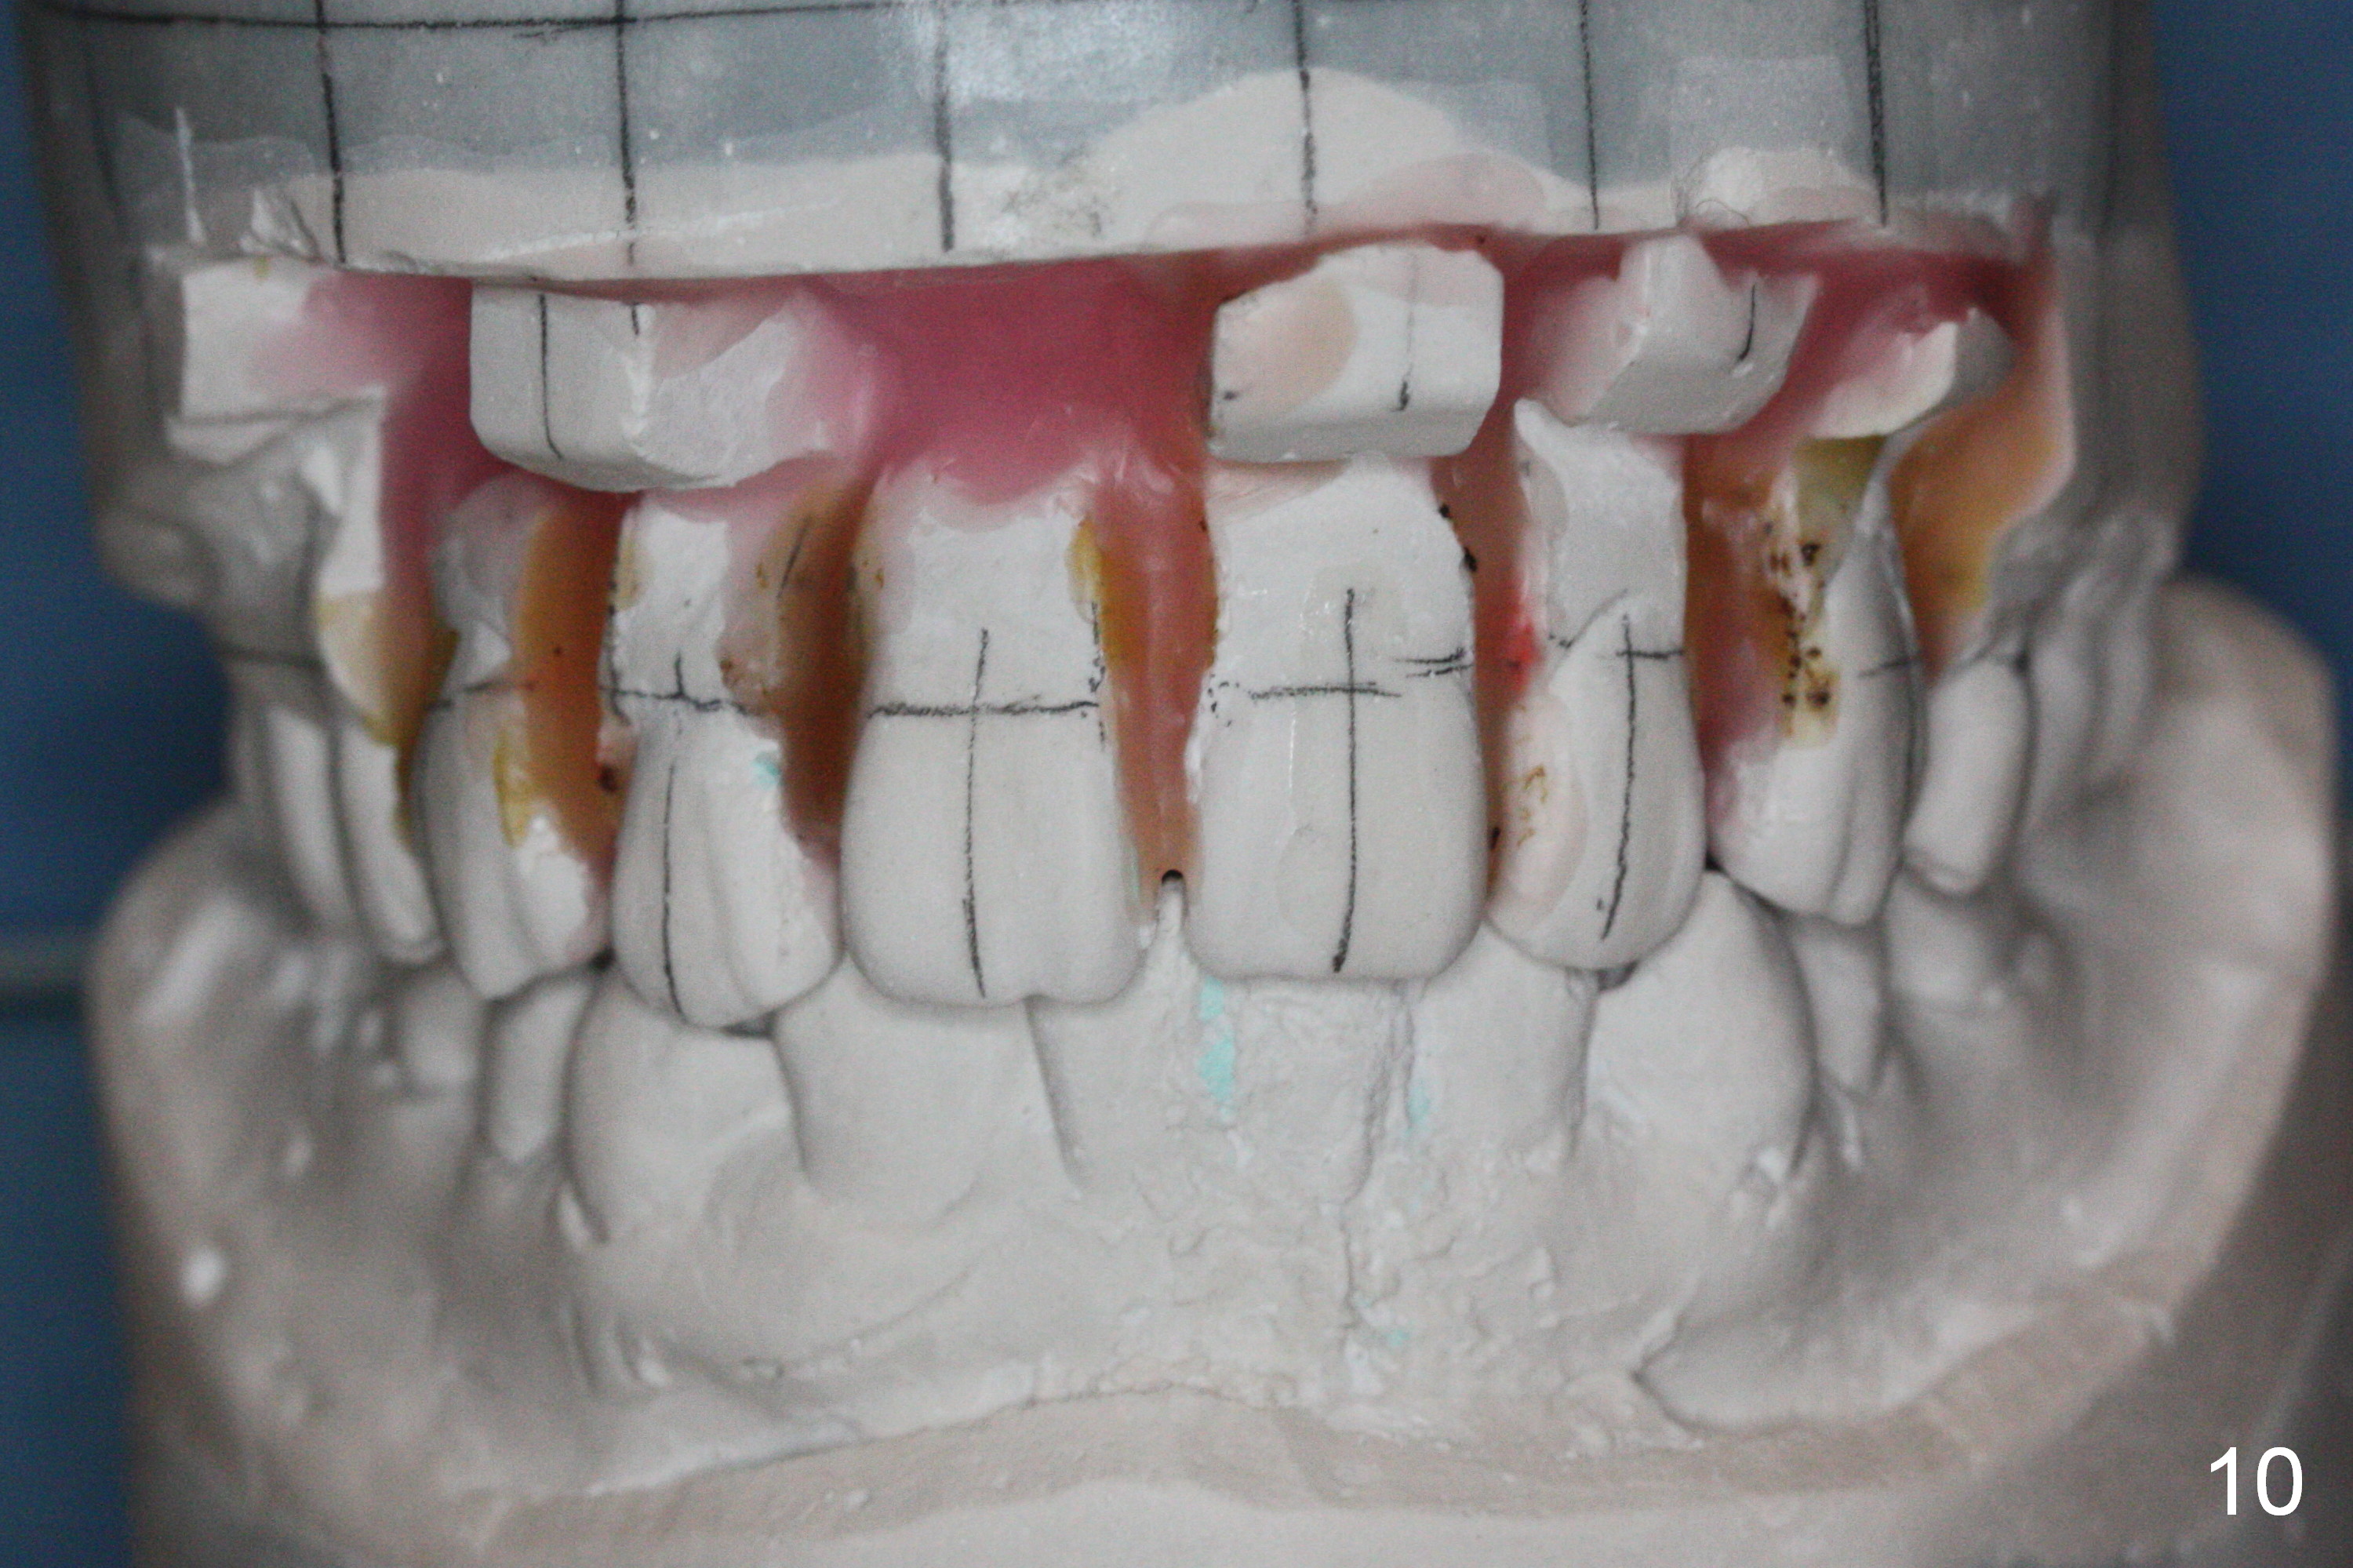

Wax up shows that there are diastemata between the upper teeth after U4s' extraction (Fig.9-11). It appears that L3s should be reduced as the incisors and that the upper posterior teeth should be mesialized. In that case, the mini-implants may be not needed.